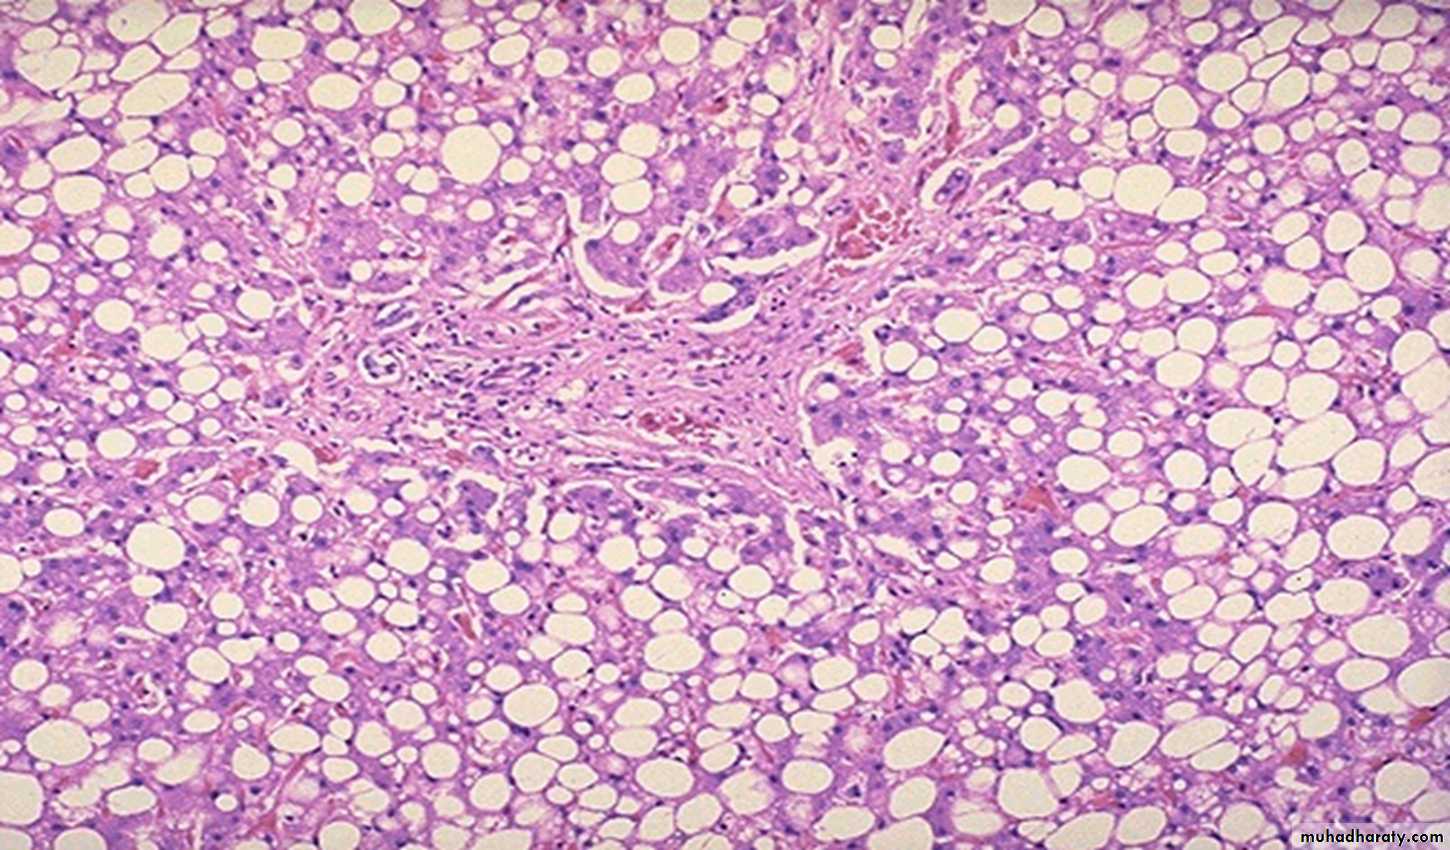

Fatty changes of the liver a large clear space of a fat inside the hepatocyte that displaces the nucleus to the periphery

Fat Droplets